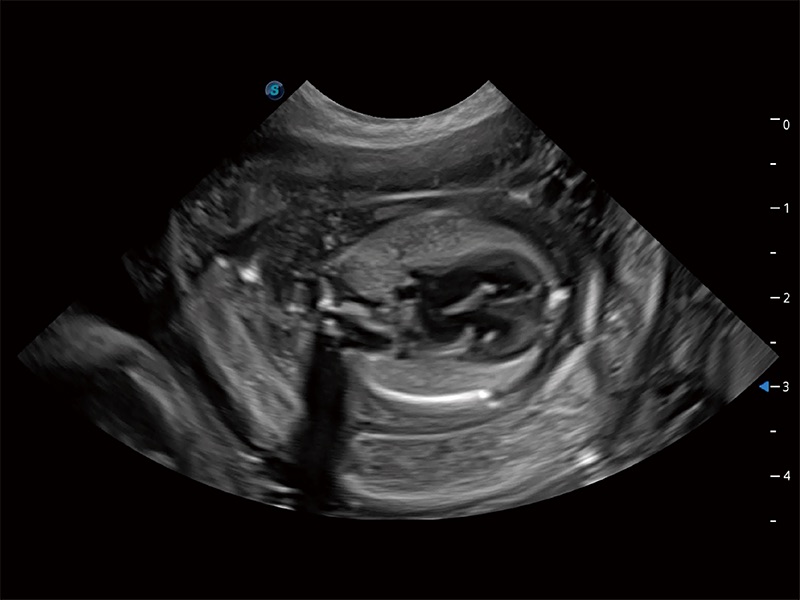

(犬)肠道

(犬)胎儿四腔心